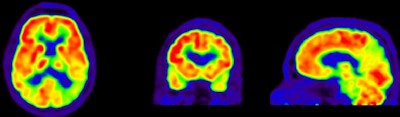

In recent years, both FDG and PiB have become more prominent biomarkers in the diagnosis of several forms of dementia, Ossenkoppele noted. PiB is designed to detect deposits of amyloid plaque in the brain, which have been associated with the onset of Alzheimer's disease. FDG measures metabolic activity of the brain at rest and has been used to distinguish between several forms of dementia.

Researchers then proceeded to the PET scans. First, patients were imaged with PiB for 90 minutes to obtain parametric images of the biomarker binding to potential clusters of amyloid. FDG-PET scans were then conducted 45 to 60 minutes after injection and lasted for 15 minutes. Standardized uptake value (SUV) ratios were calculated throughout the brain.

The resulting PET images were visually assessed by a nuclear medicine physician and reported to the neurologists to determine how the additional information changed their initial clinical diagnoses and their confidence in those interpretations.

In the Alzheimer's group, PET with PiB or FDG confirmed a total of 44 (67%) of the 66 cases prior to PET imaging. The second-greatest change was among patients with frontotemporal dementia. PET with PiB or FDG confirmed 11 (61%) of the 18 cases prior to PET.

PiB-PET scans were positive in 40 (61%) of 66 patients with clinical Alzheimer's and in five (28%) of 18 patients with clinical frontotemporal dementia. FDG SUV patterns matched the clinical diagnosis in 58% of patients with Alzheimer's and 33% of patients with clinical frontotemporal dementia, the authors noted.